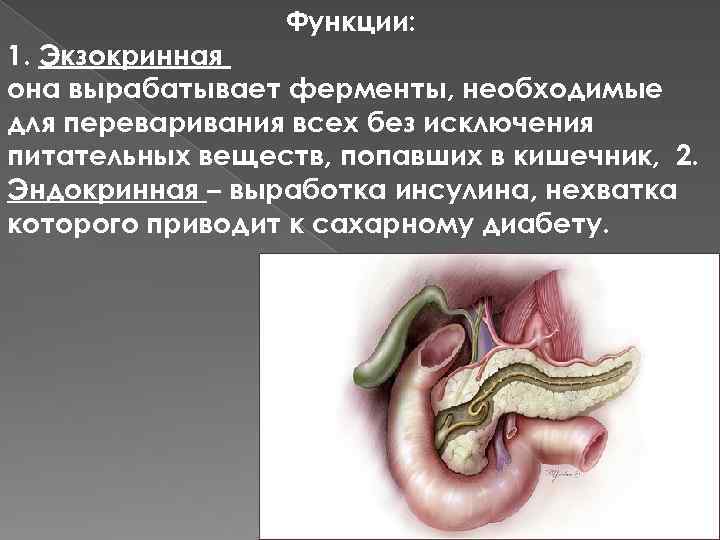

Функции: 1. Экзокринная она вырабатывает ферменты, необходимые для переваривания всех без исключения питательных веществ, попавших в кишечник, 2. Эндокринная – выработка инсулина, нехватка которого приводит к сахарному диабету.

Функции: 1. Экзокринная она вырабатывает ферменты, необходимые для переваривания всех без исключения питательных веществ, попавших в кишечник, 2. Эндокринная – выработка инсулина, нехватка которого приводит к сахарному диабету.